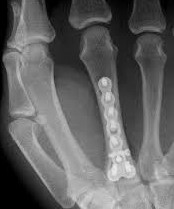

- различные виды накостного и внутрикостного остеосинтеза костей кисти и предплечья с использованием импортных и лучших представителей отечественных имплантов;